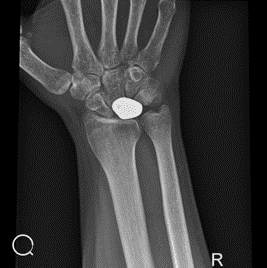

Door middelvan 3D technologie kunnen orthopedisch chirurgen een meer volledig en mee gedetailleerd beeld krijgen van botafwijkingen bij de patiënt. Deze medische analyse stelt hen in staat om een uiterst nauwkeurig behandelingsplan op maat te ontwikkelen, specifiek afgestemd op de unieke behoefte van elke patiënt.